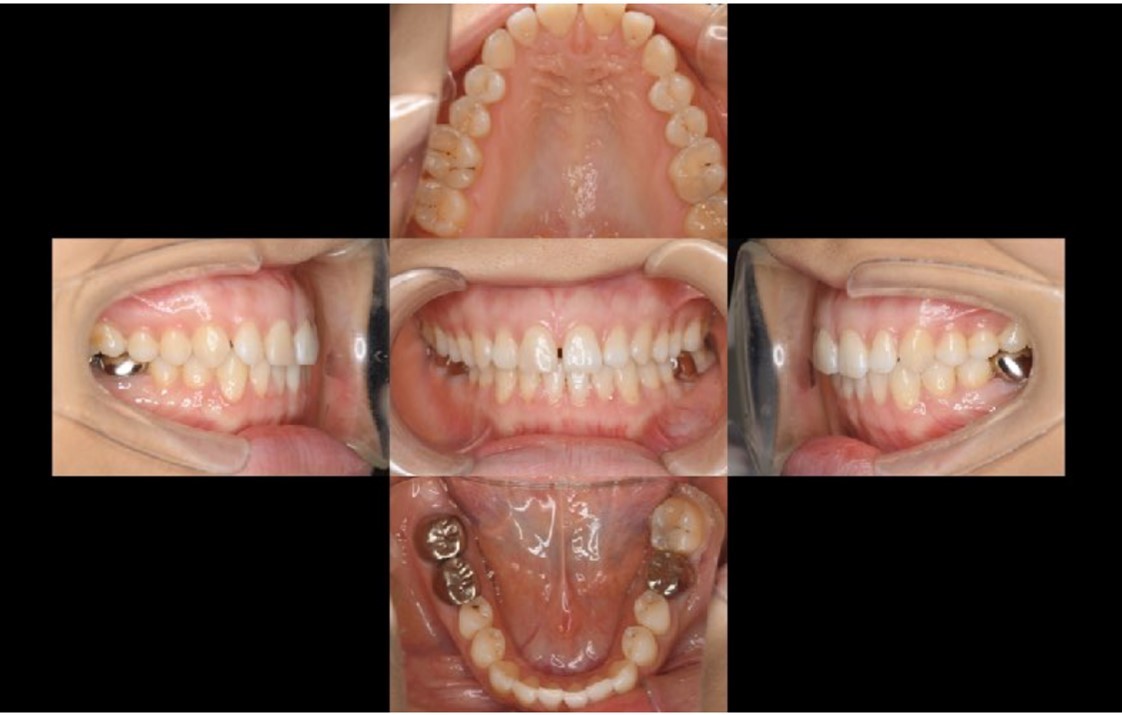

A 27-year-old female patient came to us with discomfort in the right lower jaw (Figure 1). Her primary symptoms were pain in the lower right tooth when biting and discomfort associated with not being able to chew well with the lower left single denture. The patient was married and had one young child, and previously received dental treatment in China, then had returned to Japan for childbirth and early childcare. The patient was a nonsmoker with moderate plaque control and medical history taking revealed no problems. In clinical and radiographic examinations, a root fracture was observed on tooth #46, which had been endodontic ally treated and restored with a full-cast metal crown. Periodontal probing revealed a pocket depth of 8 mm on the buccal center side of the tooth. No pain was detected with percussion and mobility of the tooth was normal. (Figure 1, Figure 2, Figure 3).

Figure 3.Preoperative intraoral findings. A metal crown was inserted at #46 and bleeding on probing during the periodontal pocket examination was noted.

Full metal crowns were inserted for #46 and #47. Pathological mobility and bleeding on probing were not seen, and the transplanted tooth showed good function.

Bone regeneration was confirmed before and after grafting, after root filling, and after placement of the prosthesis, based on X-ray imaging results (Figure 8). There was no pathologic mobility or pain during mastication, and the tooth showed good function. The patient was very satisfied with the treatment results (Figure 9).

Following the operation, root canal treatment was performed as noted above. Functions including temporary crown occlusal contact and tooth mobility, as well as pocket depth were also checked. All examination results clearly indicated placement of a definitive prosthesis in the patient (Figure 13, Figure 14). At a follow-up examination one year after surgery, progress in this case was determined to be good (Figure 15).

The patient actively visited the clinic for maintenance and showed good compliance. Achievement of occlusal recovery using auto transplantation for prosthetic treatment of the missing right and left mandibular first molars fulfilled her wishes, and created a significant improvement in functionality, thus leading to improved quality of life.